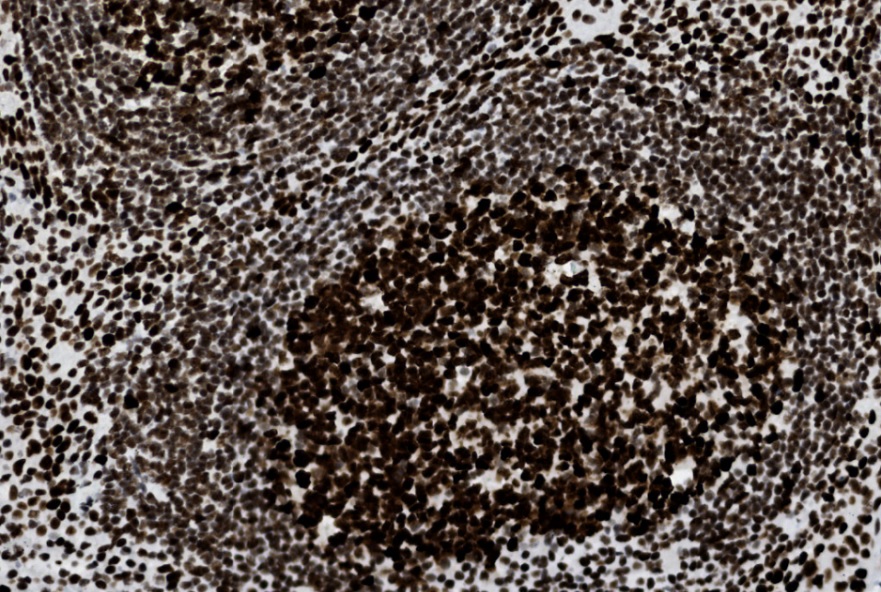

Staining pattern: Nuclear staining |

Control tissue: Tonsil, colon adenocarcinoma with loss of MSH2 |

| A moderate to strong nuclear staining reaction of the proliferating germinal centre B-cells in tonsil |

At least weak to moderate distinct nuclear staining reaction of virtually all mantle zone B-cells and interfollicular lymphocytes in tonsil |